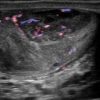

U tinh hoàn

» Thông tin: Nam giới – 35 tuổi.

» Lâm sàng: Sưng tinh hoàn.

# U tinh bào (Seminoma).